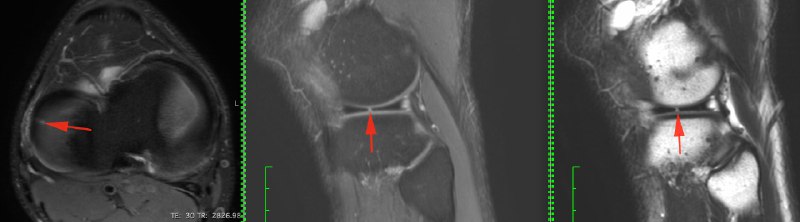

23 года, мужчина, 20 октября на матче что-то "щёлкнуло" в колене

Продолжаем диагностику по одной картинке.

Возраст 40 лет. Жалобы с прошлого воскресения - боли и хромает, травм/нагрузок не было.

Голосуем ниже